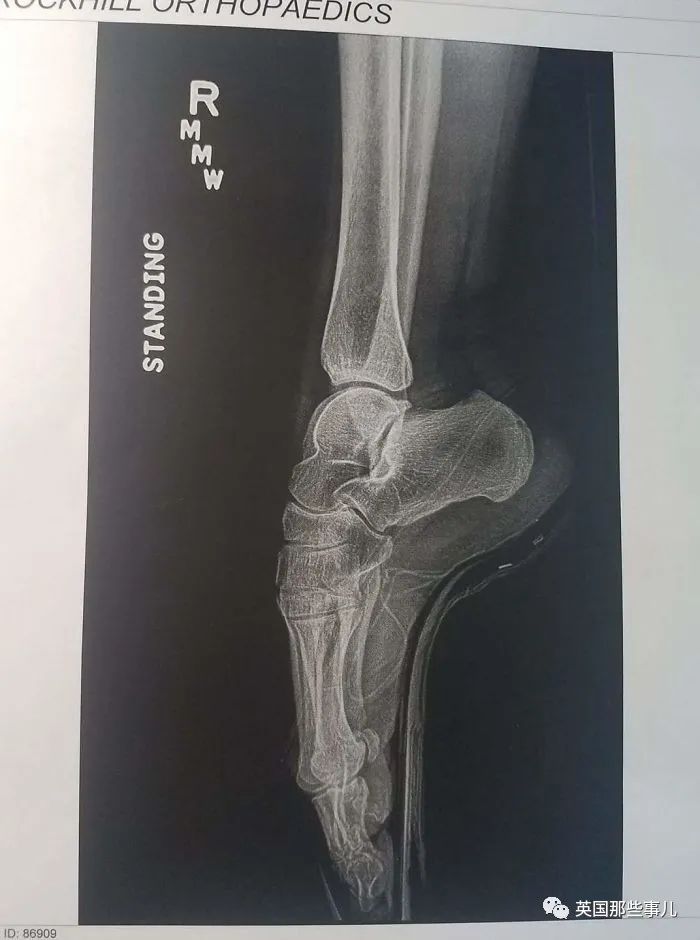

我妻子是芭蕾舞演員,這是她立起腳尖時的X光片

穿著恨天高的jio

哎呀,看著就很糟糕....